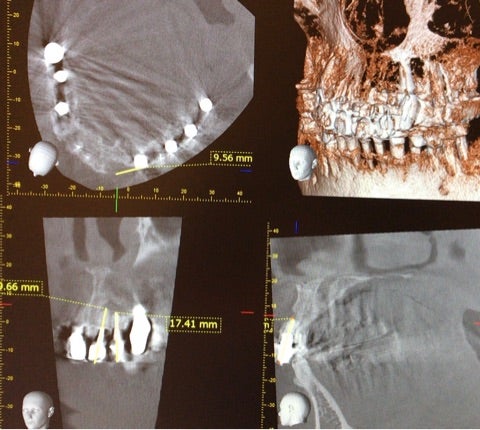

CT画像

▶︎確かに二歯を含む根尖病巣が確認でき、歯の状態は良くない事がわかります。

ただ、周囲の顎の骨がまだ残存していることや、歯の動揺が軽度であることなどを考慮し、《インプラントにした場合のメリット・デメリット》、《歯根端切除術を行った場合のメリット・デメリット》をしっかりと説明し、歯根端切除術を行い、歯を保存する治療を選択されました。